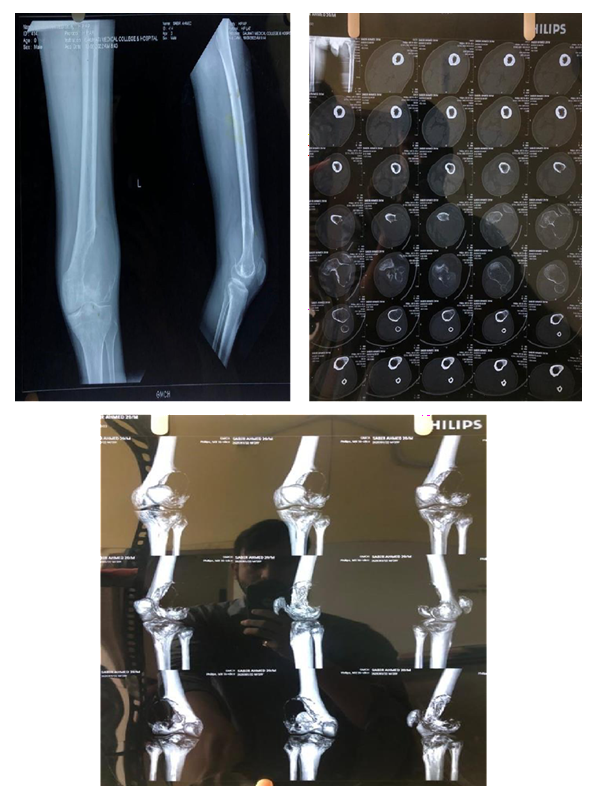

CASE 1

Diagnosis established with

MRI

Biopsy

Pre Denosumab Therapy: Break in the cortex can be clearly seen

After Neoadjuvant Denosumab Therapy

Operative Intervention

Histopathology

Followup